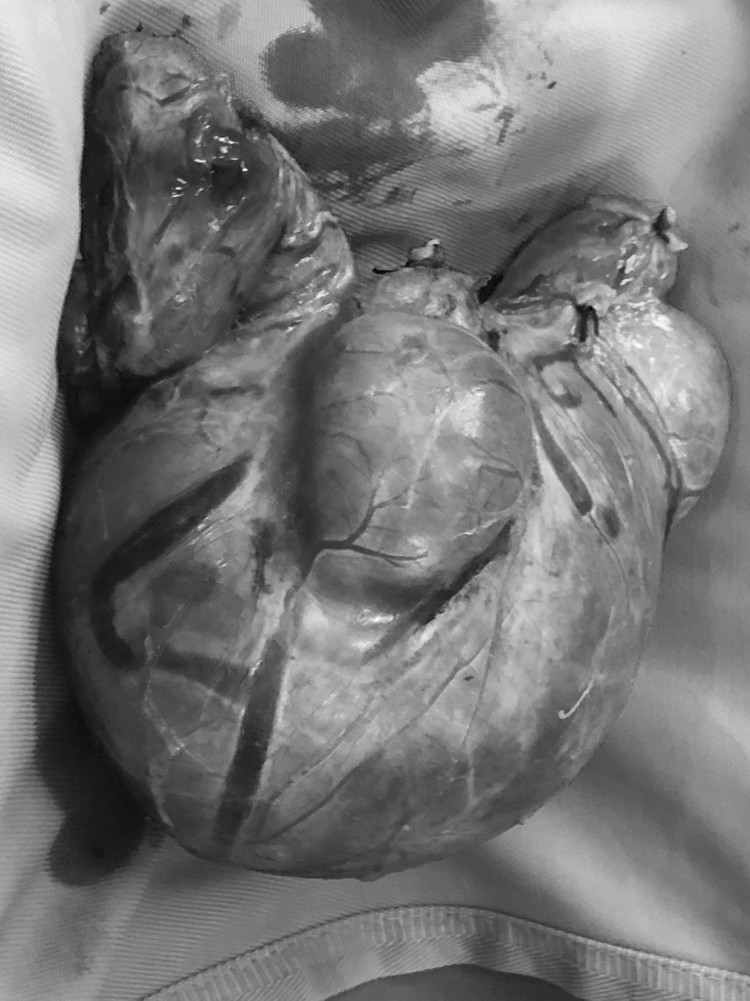

ThS.BS Nguyễn Hồng Sơn - Trưởng khoa Ung bướu, Bệnh viện đa khoa tỉnh Tuyên Quang cho biết: Đây là một ca mổ khó, khối u to, đè đẩy máng cảnh và khí quản sang phải, có nhiều đa nhân nằm 2 bên, nhân to nhất kích thước (10x15) cm.

| Khối bướu cổ khổng lồ được lấy ra |

Trong vòng 2 giờ, kíp mổ đã tiến hành phẫu tích cắt toàn bộ khối u và tuyến giáp, bảo tồn tuyến cận giáp và dây thần kinh quặt ngược 2 bên, thực hiện cầm máu kỹ, đặt dẫn lưu sau đó khâu đóng vết thương 2 lớp cho bệnh nhân.